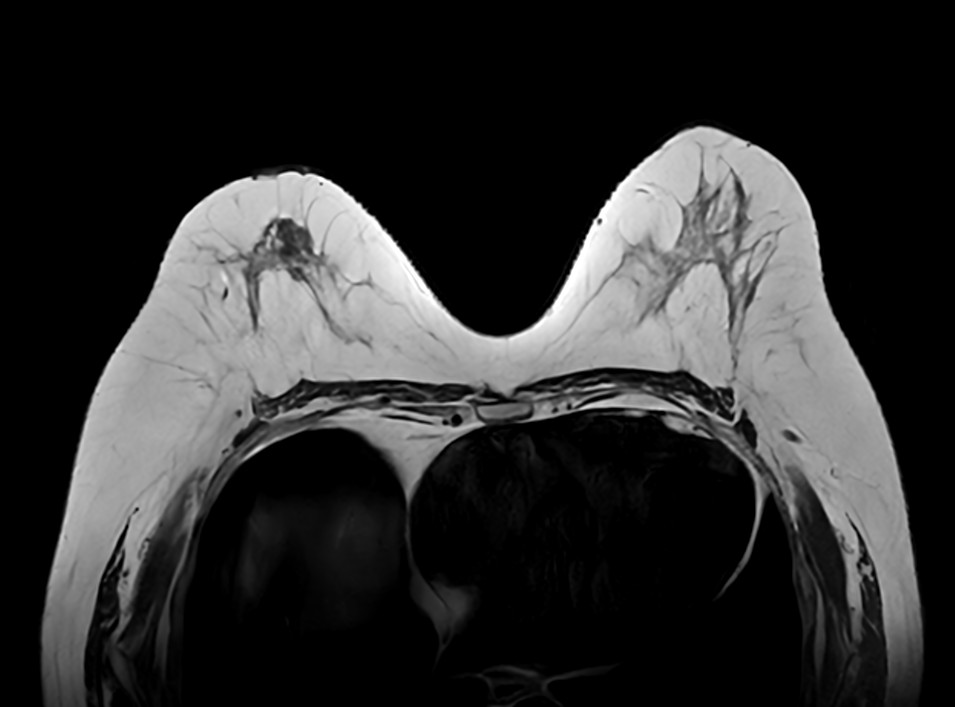

Axial T1w mDIXON FFE (Water only)